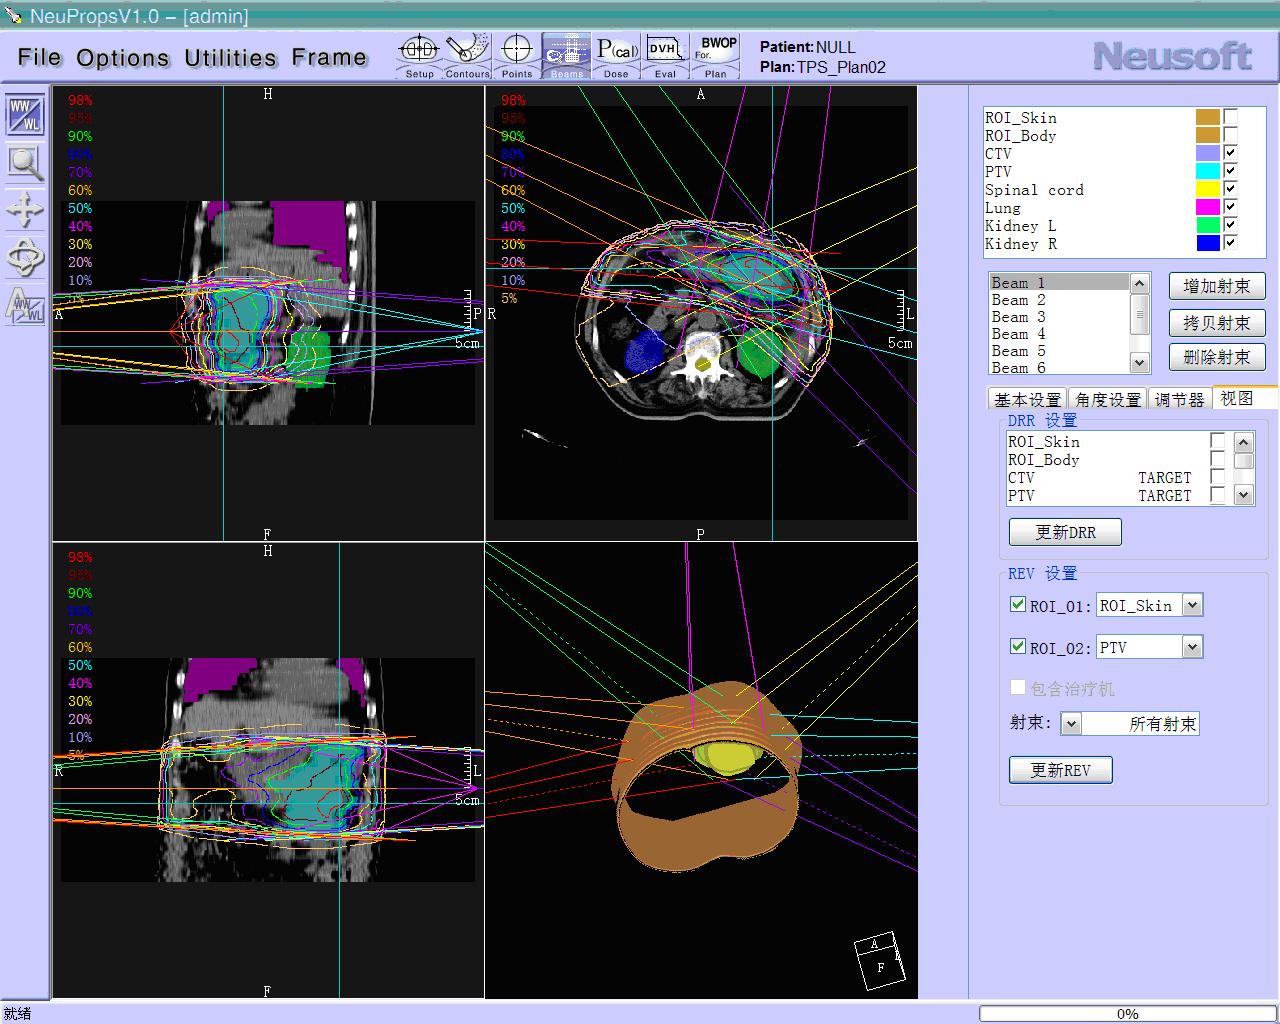

Segmentation

Segmentation of tissue (e.g., isolating the brain, differentiating gray and white matter) is performed using region-growing methods, filter operations as well as the application of 3D templates. Using the mouse it is very easy to explore a 3D volume with superimposed pseudocolor-coded statistical maps in a four-window representation showing a sagittal, coronal, transversal and oblique section. Based on a (segmented) 3D data set a three-dimensional reconstruction of the subjects' head and brain can be calculated and displayed from any specified viewpoint using volume or surface rendering.

Volume Rendering

Volume rendering is performed with a very fast ray casting algorithm; lightning calculations are based on Phong-shading. Surface rendering of reconstructed surfaces is performed using OpenGL. Using texture mapping, a reconstructed surface (e.g., head or brain) may be sliced in real time, showing both surface and volume data at the same time. Initial polygon meshes serve as the basis for surface finding, cortex inflation and cortex flattening computations.